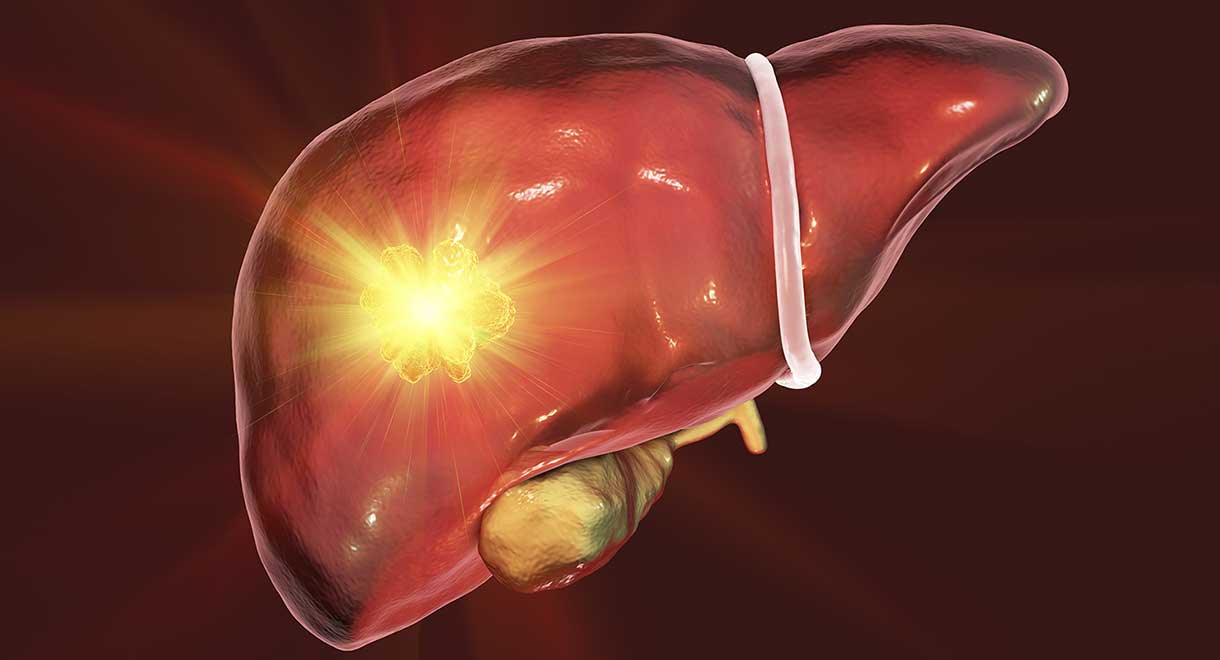

Изображения заболеваний печени: признаки и симптомы